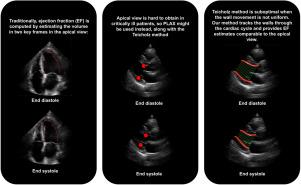

The left ventricular ejection fraction is a key metric for evaluating the systolic function in critically ill patients. Traditionally, it is computed using apical 2- and 4-chamber views in an echocardiogram; however, obtaining these views in an acutely ill patient in the emergency department is often difficult. A parasternal long-axis view, acquired with point of care ultrasound, is a faster and easier alternative. Unfortunately, the methods for estimating the ejection fraction from this view underperform when the left ventricular wall movement is not uniform or when its shape is not properly modeled as an ellipsoid. We propose a novel method that tracks the movement of the visible portions of the walls during the full cardiac cycle, and then estimates the ejection fraction based on that movement.